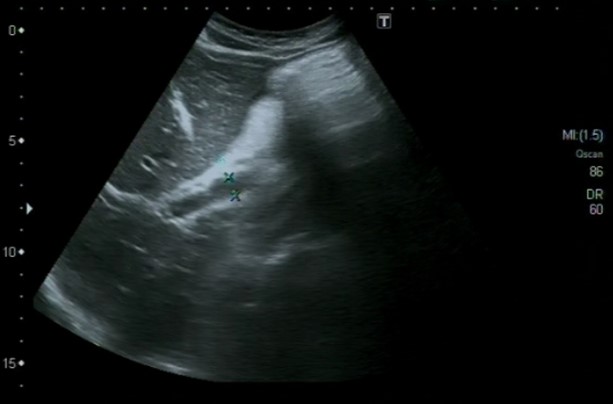

Hallazgos ecográficos

Ascitis a estudio, sugestiva de peritonitis tuberculosa

La ecografía clínica es una herramienta esencial en el diagnóstico de la ascitis. Permite la identificación y cuantificación precisa del líquido, además de evaluar su distribución. La realización de paracentesis guiada por ecografía es fundamental para establecer la causa subyacente de la ascitis, permitiendo obtener muestras de líquido para su análisis. La combinación de la ecografía y la paracentesis mejora la precisión diagnóstica y guía la atención médica apropiada.